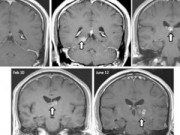

Hình ảnh con sán dài 8cm làm tổ trong não bé trai 11 tuổi

Shanghaiist đưa tin, các bác sỹ tại Bệnh viện Xinhua, Thượng Hải, Trung Quốc, vừa tiến hành phẫu thuật loại bỏ con sán dây dài 8cm sống ký sinh trong não bé trai 11 tuổi sau khi cậu bé liên tục bị các cơn co giật.

Các bác sỹ xác nhận bé trai bị nhiễm sán sparganosis, chứng bệnh dẫn tới các cơn tai biến, suy giảm trí nhớ và đau đầu.